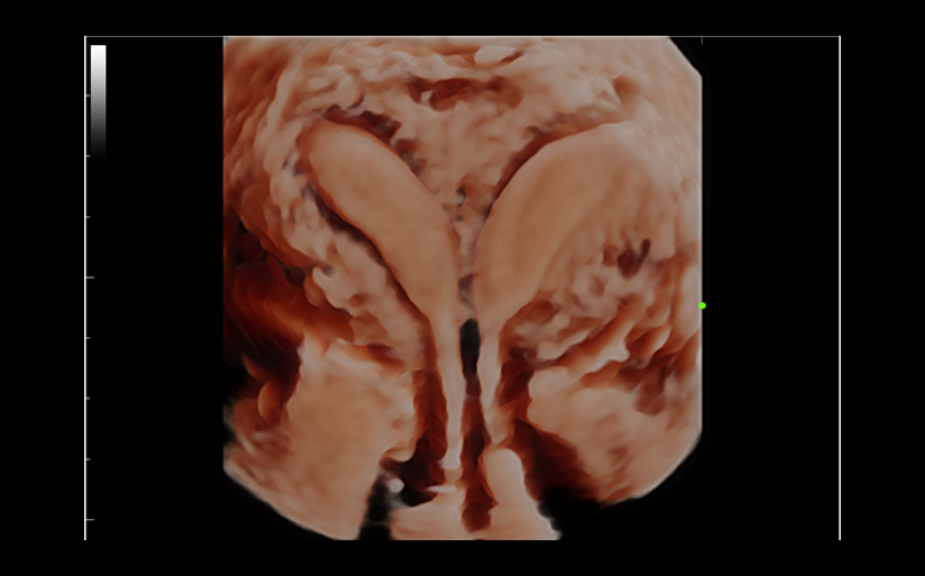

ImГЎgenes ClГӯnicas